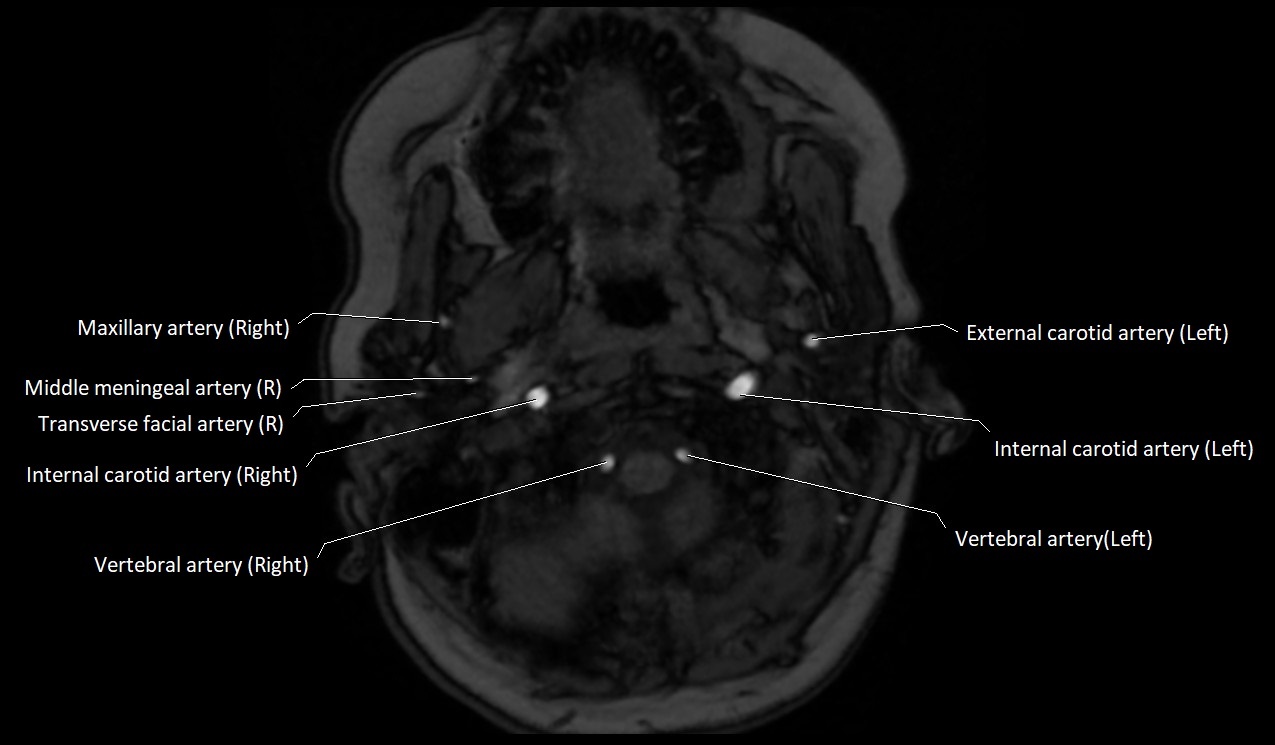

MRI images

image